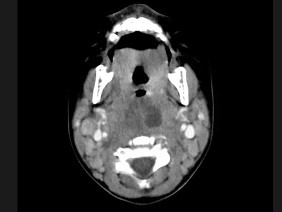

[多选题] 10个月大的婴儿,发热,曾患中耳炎,CT扫描如图所示,正确的描述或诊断是()A . 咽后壁软组织肿胀B . 其内密度不均C . 颈椎骨质未见明显异常D . 咽后壁脓肿E . 咽后壁寒性脓肿